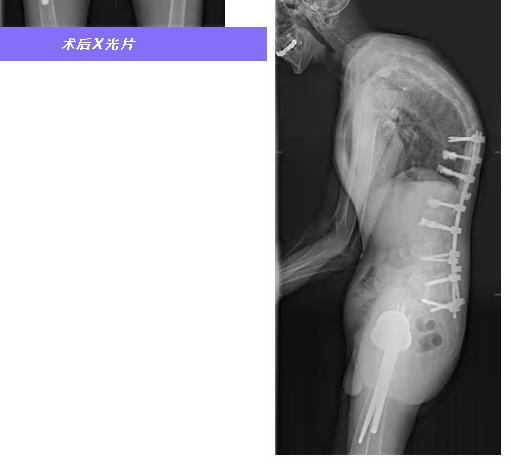

2024 年 10 月,王龙怀着最后的希望来到青海红十字医院。在这里,阿尖措教授、邝磊教授、李占银教授带领的脊柱外科团队和郭立平教授带领的关节骨科团队接过了拯救他的接力棒,为其制定了详尽的治疗方案。医疗团队凭借精湛医术,先后为他实施了 2 次脊柱后凸畸形截骨矫正手术和 2 次人工髋关节置换手术,逐步将他折叠的身体打开。2024 年 12 月,王龙终于完成了全部治疗,身高从原来的 132 厘米增长至 168 厘米。在整个治疗过程中,智善公益基金会为他的治疗费用兜底,最终医保结算之后实现了免费医疗,为这个贫困的家庭给予了极大的经济支持。